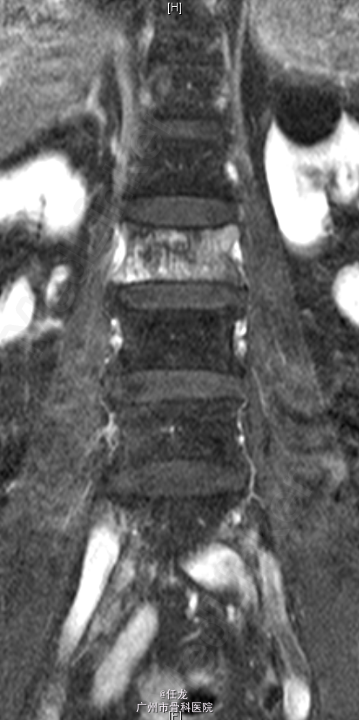

主诉:前列腺癌术后8年,反复腰痛半年,加重2周。 病史:患者8年前曾诊断为前列腺癌,并在外院行手术治疗,并多次放疗,一般坚持门诊复查。半年前出现腰部疼痛,为持续性疼痛,休息后无缓解,无双下肢麻木疼痛。最近两周加重明显,影响睡眠。遂至门诊就诊,门诊MRI考虑:前列腺癌腰椎转,故收入院作进一步诊治,患者一般情况较差。

查体:L2-L4棘突及棘旁轻度叩压痛。四肢感觉、肌力及肌张力正常。双侧坐骨神经出口处无轻压痛。双侧直腿抬高试验(-),双侧股神经牵拉试验(-)。双侧膝反射及踝反射未引出,双侧踝阵挛阴性。双侧Babinski 征及Oppenheim 征(-)。 辅助检查:PSA:73.22ng/ml ↑。腰椎影像学检查如下。

诊断:1. 前列腺癌腰椎转移 2.前列腺癌切除术后 处理:入院后完善相关检查,术前给予对症治疗,科里术前讨论决定:拟行手术:L2-4经皮穿刺活检+术中放疗+椎体成形术。